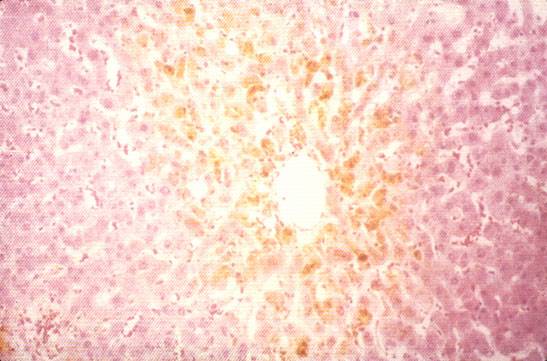

Cholate stasis

Fig 52 - CHOLATE STASIS: The periportal hepatocytes are swollen, hydropic and foamy, pseudoxanthomatous cells. These are the changes of so-called "biliary piece meal necrosis" that occurs in stagnation of bile flow. The changes are attributed to retention of bile acids. This sample is from a case of primary biliary cirrhosis (PBC).